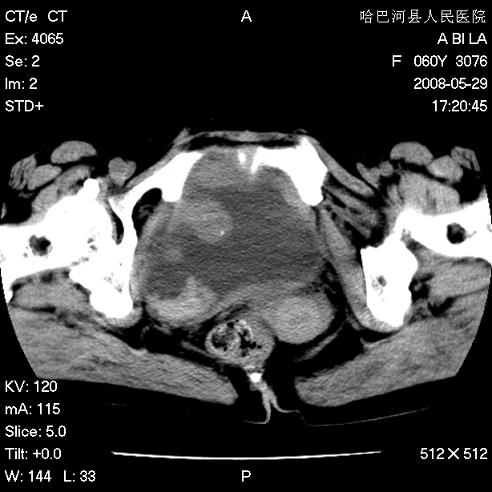

标题: CT13730:排尿不畅4天,抗炎治疗无效,现尿中可见血块 [打印本页]

标题: CT13730:排尿不畅4天,抗炎治疗无效,现尿中可见血块

手术结果及病理:膀胱癌并膀胱壁转移,膀胱内血块